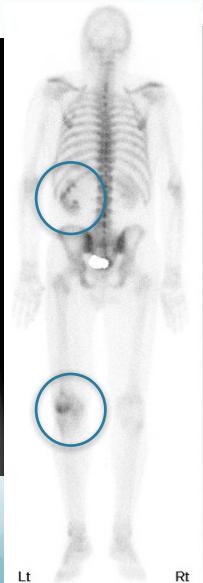

- Bone scan

- Common sites:

- Vertebrae, pelvis, Proximal femur and humerus